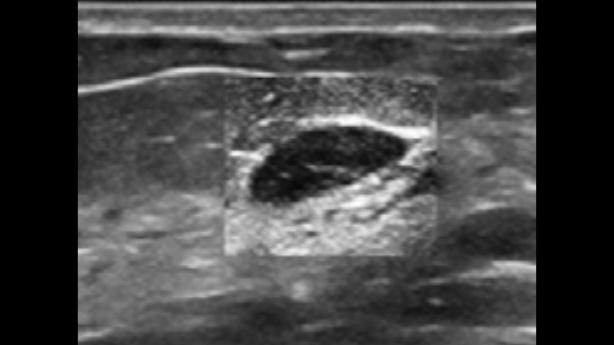

System ultrasonograficzny Zeus jest wyposa?ony w?przyjazny interfejs u?ytkownika i??atwe w?u?yciu funkcje umo?liwiaj?ce skuteczne skanowanie. Jego wszechstronne funkcje obejmuj? ultrasonografi? jamy brzusznej, naczyniow?, ma?ych narz?d├│w i?uk?adu mi??niowo-szkieletowego, zwi?kszaj?c pewno?? diagnostyczn?.